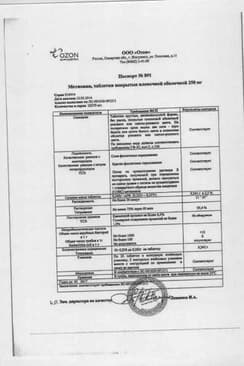

Состав препарата Метионин

Таблетки, покрытые оболочкой розового цвета, круглые, двояковыпуклые; на поперечном разрезе видны два слоя.

1 таб.

метионин 250 мг

Вспомогательные вещества: крахмал картофельный, кремния диоксид коллоидный, кальция стеарат, полисорбат 80, сахароза, патока крахмальная, мука пшеничная, азорубин (краситель кислотный красный), воск пчелиный, масло подсолнечника.

10 шт. - упаковки ячейковые контурные (5) - пачки картонные.

Сертификаты